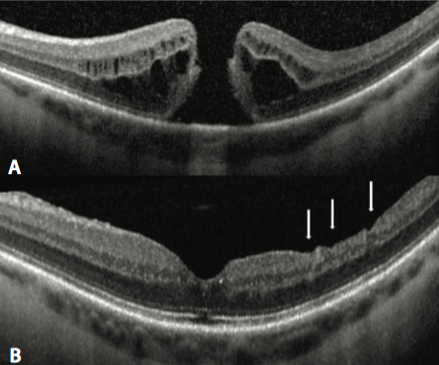

Fue un estudio prospectivo, comparativo e intervencional, se incluyeron 50 pacientes, dividiendo 2 grupos, el grupo 1 con 25 ojos de pelado pequeño (3mm) y mientras el grupo 2 de 25 ojos con pelado grande (5 mm). En los resultados se obtuvo que las tasas de cierre del agujero macular eran similares en ambos grupos sin ser significativas (p=0,20). Ninguna diferencia se encontró con respecto al éxito anatómico, respecto al tamaño, estadio o duración del agujero. La agudeza visual fue mejor en el grupo 1 (4 lineas vs 2 lineas del ETDRS P= 0,04); la capa de fibras nerviosas fue más delgada en el grupo 2 (5mm), en la región a 2.5 mm temporal donde fue significativo, (P < 0.05), mientras que la capa de células ganglionares fue más gruesa en el grupo de 3mm en región temporal predominantemente.

Este reciente estudio prueba claramente que el hecho de incrementar el tamaño del pelado no influye sobre la tasa de cierre anatómica, independientemente del tamaño, duración o fase de evolución del agujero y si puede influir negativamente sobre el grosor de la capa de fibras nerviosas y de células ganglionares.

La reciente evidencia muestra que aunque el pelado de la MLI no mejore los resultados sobre la agudeza visual, si lo es respecto a los resultados anatómicos, siendo por lo tanto más favorable en términos de costo-efectividad, por incrementar la probabilidad de cierre anatómico. Sin embargo debemos hacer una lectura cuidadosa recordando que en el agujero macular el pelado de la MLI, se debe procurar mantener un tamaño tan pequeño como sea posible, justo lo suficiente para liberar la tracción tangencial alrededor del agujero y maximizar los resultados funcionales sin comprometer las tasas de éxito de cierre quirúrgico primarias.